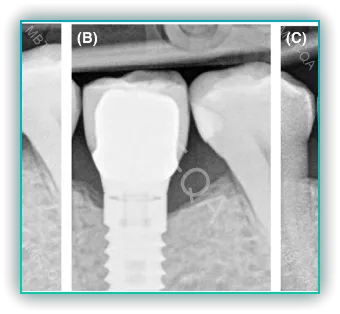

2. 임플란트 주변의 잇몸뼈 변화는 임플란트의 형태에 영향을 받습니다. 임플란트 식립 후 잇몸뼈가 상대적으로 흡수되면서 임플란트가 길어 보일 수 있으며, 이는 미적으로 불리한 상황을 만들 수 있습니다.

3. 임플란트의 형태는 환자의 입 모양에 영향을 미치며, 미적인 문제뿐만 아니라 기능적인 문제를 일으킬 수 있습니다. 이는 잇몸뼈의 변화와 연관되어 임플란트가 튀어나오거나 길어 보이는 현상을 유발할 수 있습니다.

앞니 임플란트를 실시할 때, 주변 뼈 소실 문제는 중요한 고려 사항입니다. 임플란트 주변의 뼈가 소실되면 임플란트의 안정성과 지속성에 영향을 미칠 수 있으며, 심미적인 문제도 발생할 수 있습니다.

임플란트 주변 뼈 소실의 원인은 다양합니다. 치아를 뽑게 되면, 해당 부위의 뼈가 자연스럽게 흡수되기 시작합니다. 이러한 뼈 소실은 임플란트가 제대로 고정되지 않는 문제를 유발할 수 있습니다. 또한, 임플란트 식립 후에도 뼈의 소실이 계속될 수 있으며, 이는 임플란트의 장기적인 성공에 영향을 줄 수 있습니다.